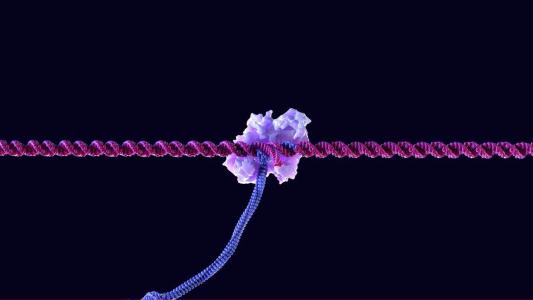

Small protein, big breakthrough for CRISPR gene editing

A new protein opens doors for gene editing by gaining access to hard-to-reach areas of the genome.

For the first time, researchers edit human mitochondrial DNA

Researchers can now edit a part of the human genome that CRISPR has never been able to. This opens up new possibilities for research and cures for devastating rare genetic diseases.